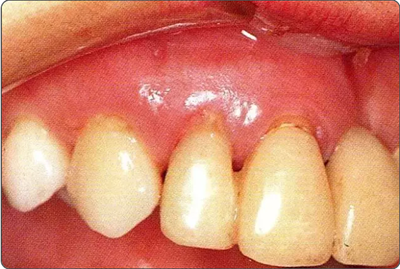

圖10-9  術(shù)后2周的狀態(tài)。牙齦乳頭獲得保存。較之使用GTR膜,自體骨移植更不容易引起牙齦乳頭的壞死。